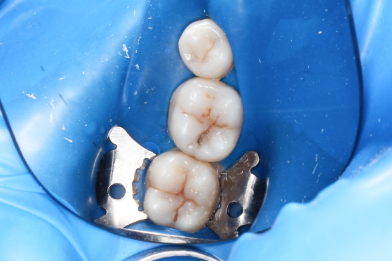

Д.12 лет. Жалобы на реакцию, на сладкое и холодное между зубами 16,15.

Колиш Максим Петрович

При осмотре обнаружен контактный кариес на зубах 16,15.

Лечение в один визит, восстановление функциональности композитной реставрацией. -